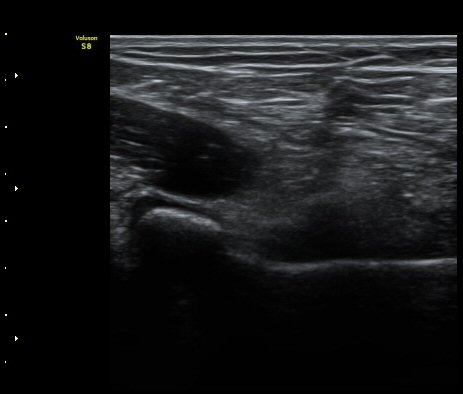

ÆÈ²ÞÄ¡ ³»Ãø¿¡¼­ ½ÃÇàÇÑ ¿ä°ñµÎ Á¾´Ü¸é°Ë»ç¿¡¼­ ¿ä°ñµÎ ÇÇÁú°ñÀÇ ºÒ±ÔÄ¥º¯È­(irregularity)°¡

°üÂûµÇ¾î ¼Õ»óÀÌ ÃßÁ¤µÊ(±×¸² 3)